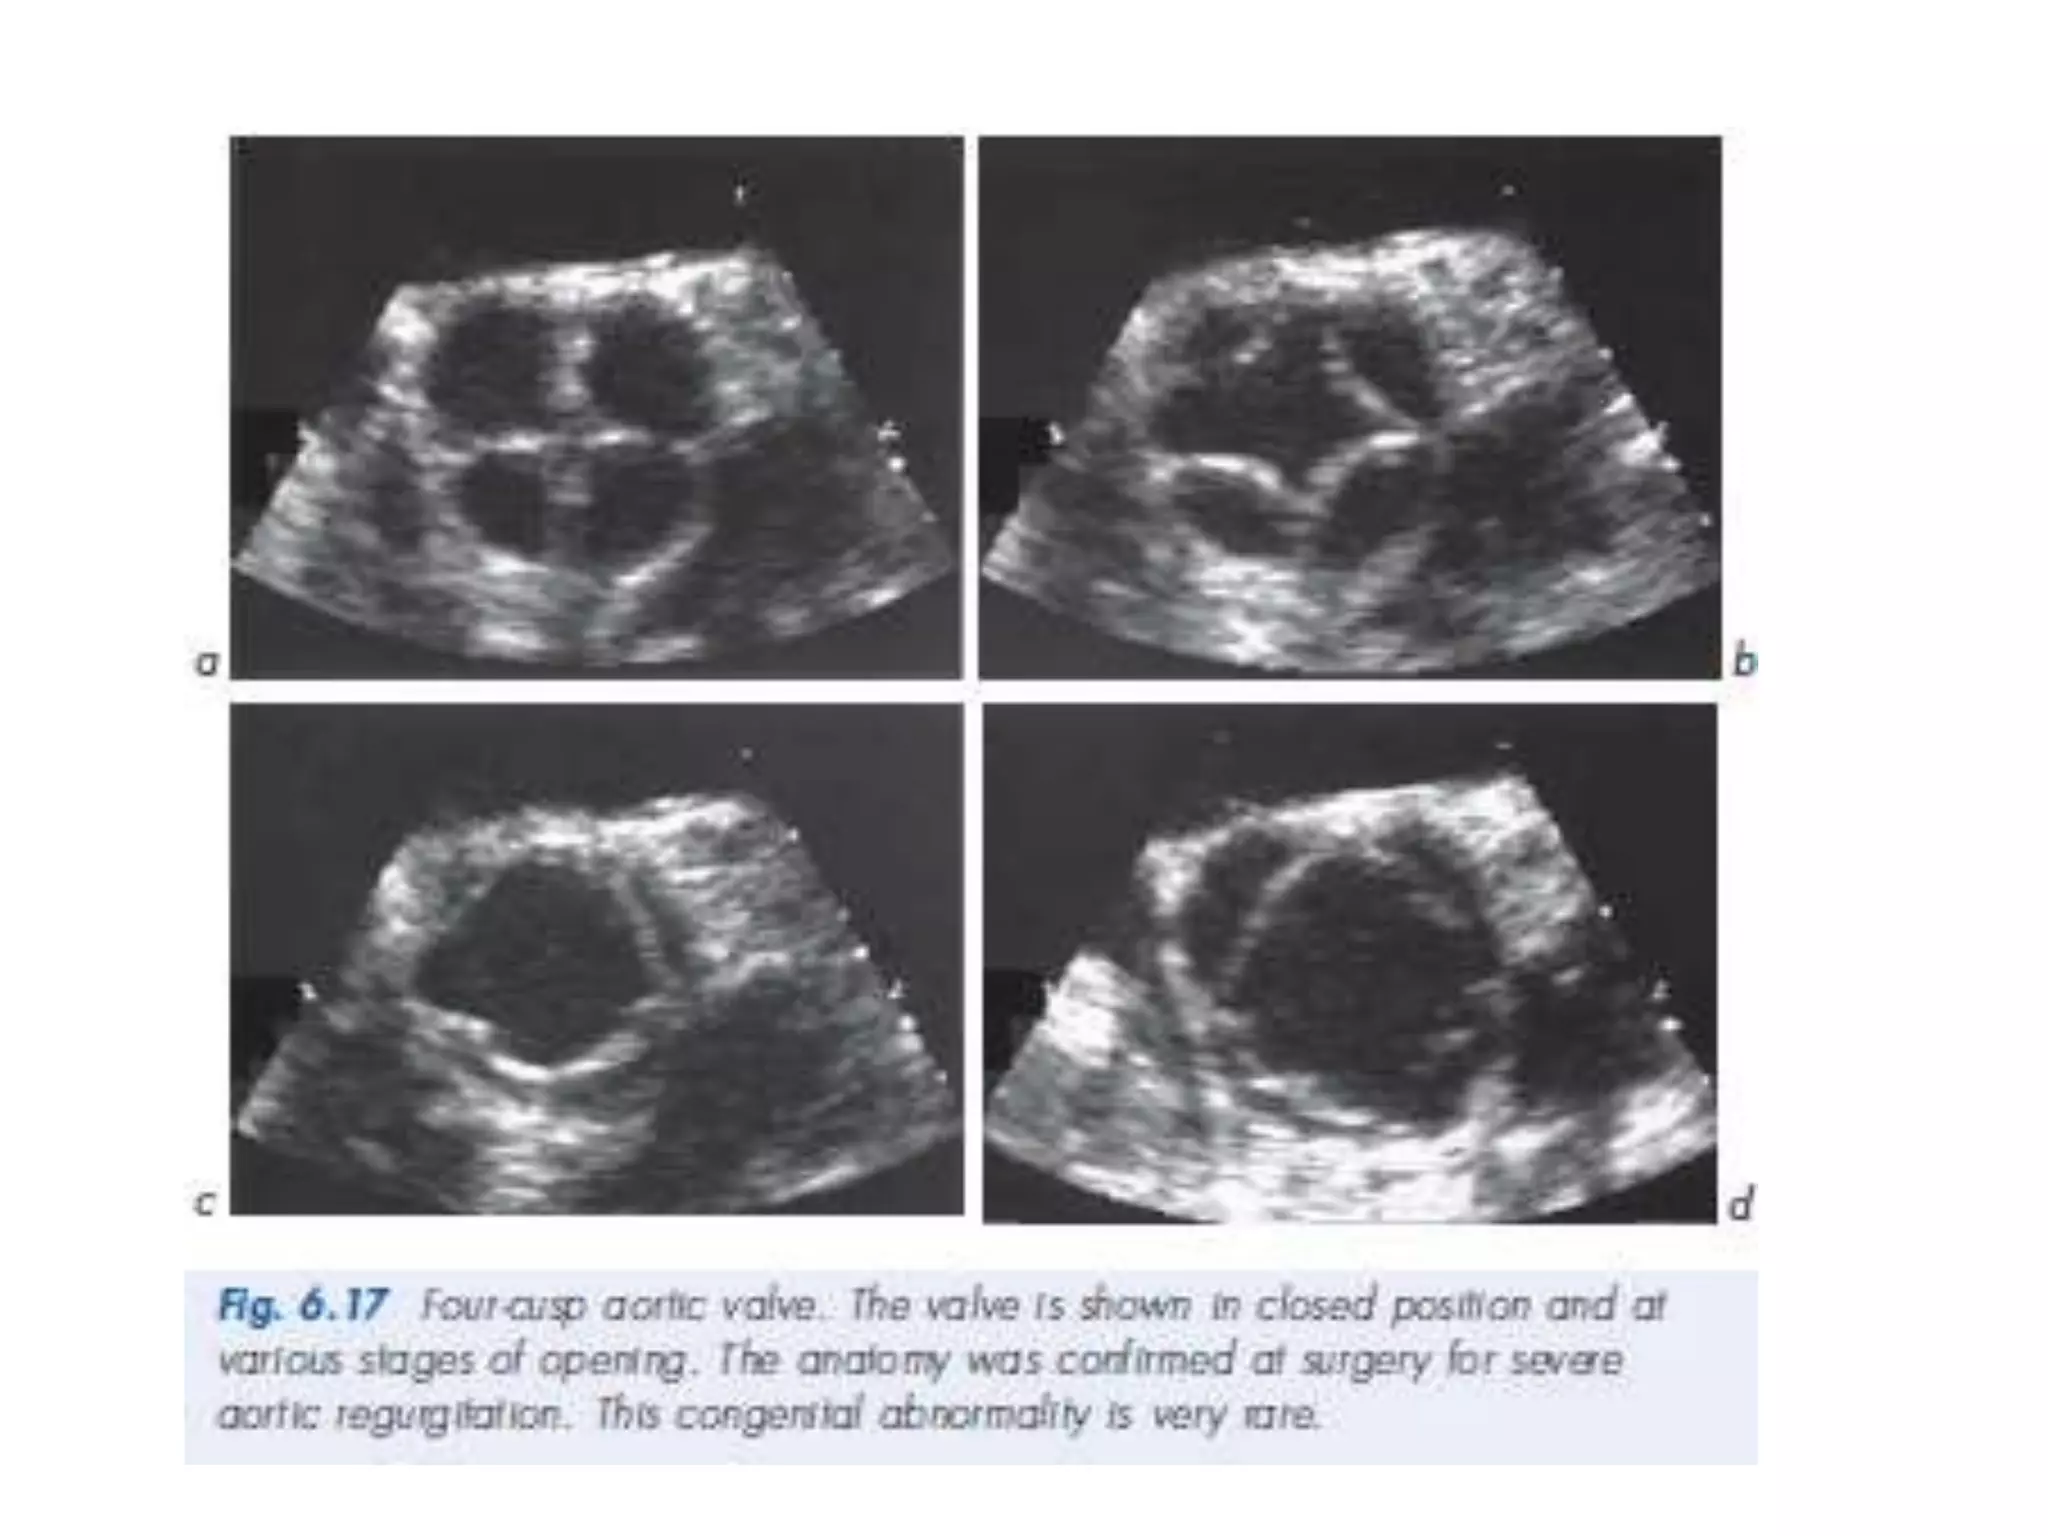

Bicuspid Aortic Valve